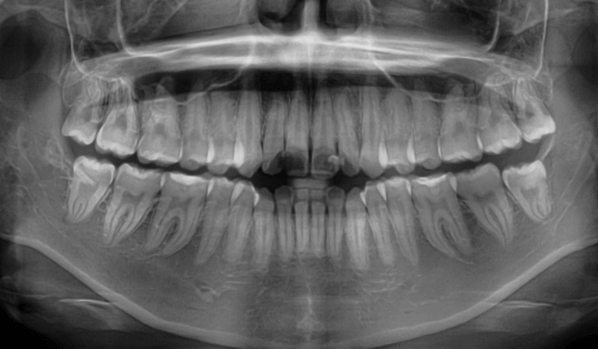

| 年齢・性別 | 25歳女性 |

|---|---|

| 主訴 | 前歯の歯並びの乱れ(叢生)を気にされて来院された。咬み合わせや審美的な改善を希望されていました。 |

| 治療期間・回数 | 4年5ヶ月・30回 |

| 費用 | 1100,000円(税別) |